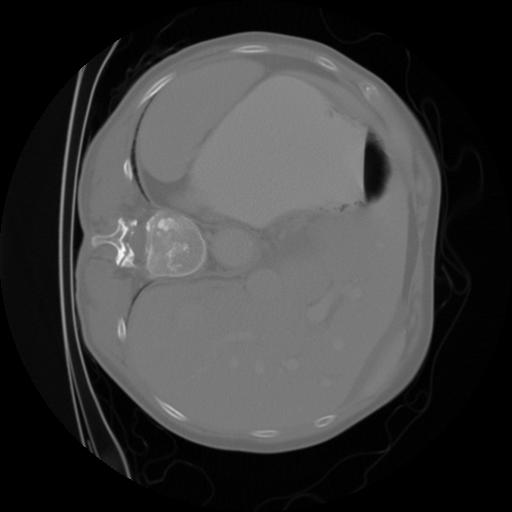

这是我的CT看起来的一个例子,尽管有些CT看起来有点不同,因为它们的质量比这个例子要低: